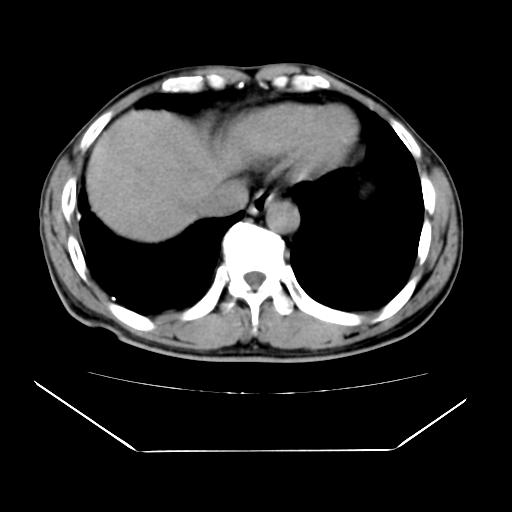

男性,55岁,外院体检afp明显升高,但b超未发现异常,否认乙肝病史。来我院ct增强。有延时扫描。

延时扫描完全充填,血管瘤

肝脏右叶动脉期可见低密度影,至延迟期被充填,考虑血管瘤可能性大。

肝右叶病灶

不排除肝右叶肝癌可能。

如果这个是癌灶的话则下腔静脉有瘤栓可能

肝6段血管瘤

血管瘤可能性大。

考虑肝右静脉影。